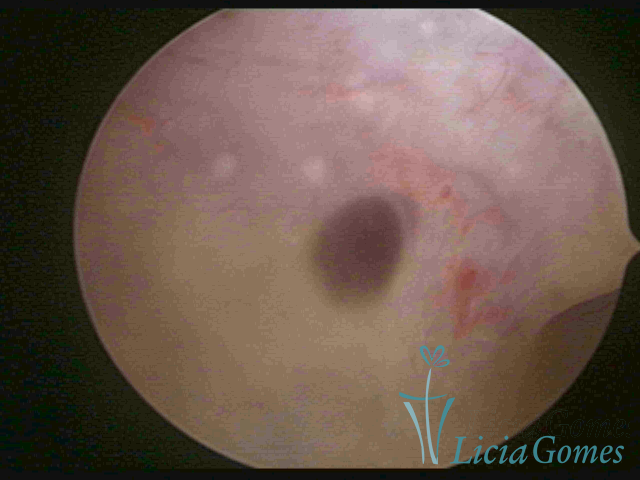

ADENOMIOSE

É a presença de tecido endometrial na camada muscular do útero

A vídeo-histeroscopia permite diagnosticar às lesões próximas às camadas miometriais superficiais, próximo ao endométrio visualizando lesões de coloração violácea, circunscritas, ou acastanhadas com conteúdo achocolatado.